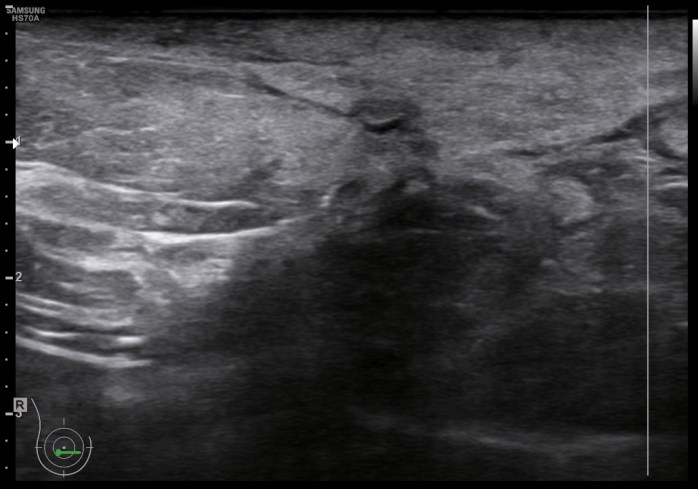

La clínica ya la conocemos, la semiología os la presento aquí. Ecográficamente la mastitis se ve como una zona donde el tejido varía la ecogenicidad, se vuelve más hiperecogénico, aumena su tamaño, incluso su vascularización. La piel se puede ver engrosada. El tejido mamario puede verse heterogéneo, simulando lesiones de otra índole, es decir, su aspecto puede ser variado.

Ecográficamente, encontraremos una zona afectada, de la manera descrita en el párrafo superior, y junto a ella, en una zona normal, sin afectación la semiología normal de la mama.

La imagen 1 y la imagen 2 son normalidad con anatomía básica y semilogía patológica respectivamente. Compara amabas imágenes para darte cuenta de como cambia el tejido afecto por la mastitis en este caso. No olvides que hay otras patología que pueden afectar el tejido modificando su ecoestructura normal de forma similar.